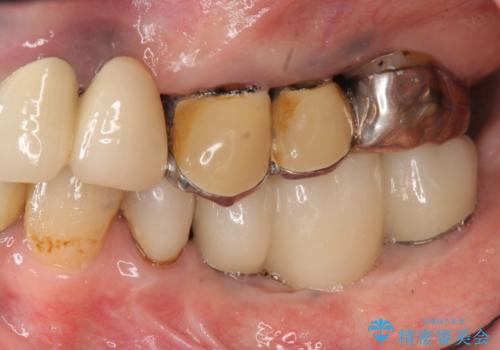

- 「他院で虫歯治療を行っているが、延々終わらず数年経過している。全体的な治療を希望したい。」と全顎的な治療を希望され来院されました。

・再発した虫歯

・銀歯の下にできた虫歯

・根尖性歯周炎

・残根状態の歯

など、虫歯を原因とする問題が多発した状態です。

今後延々と治療を繰り返さないために、全ての銀歯を外し虫歯を丁寧に取り切り、根管治療を行い、残せない歯は抜去を行った上でインプラント治療を行っていくことで全体的な治療を計画していくこととなりました。